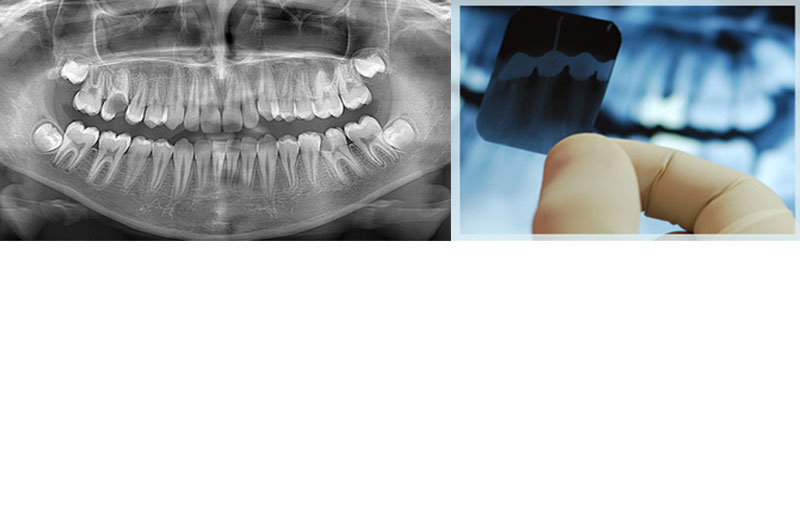

oral diagnoz radyoloji

Oral Diagnoz, Radyoloji Hizmetleri

Panaromik Radyografiler

Panaromik radyografiler, ağızdaki mevcut dişlerin tamamını, gömük dişleri, dişleri çevreleyen kemik dokusunu, çene kemiğinin tamamını, ağız gölgesindeki fizyolojik ve patolojik boşlukları ve eklemleri tek seferde ve aynı görüntü içerisinde incelemeye olanak sağlayan bir ağız dışı görüntüleme tekniğidir. Özellikle kontrol amaçlı genel ağız muayenesinde, gömük diş çekimi, rezeksiyon, ufak kistler veya az sayıda implant uygulanması gibi basit cerrahi işlemlerde kullanılır. Tüm dişlerin tek seferde görüntülenmesi, seri periapikal çekimlere oranla hastanın daha az radyasyona maruz kalmasını sağlarken, hekime de genel bir değerlendirme yapabilme şansı tanır.